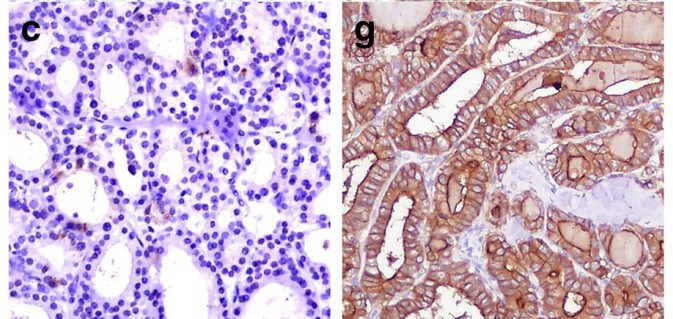

Microphotograph demonstrating the expression of HBME-1 in follicular adenoma and follicular variant of papillary carcinoma (Left: absence of immunoexpression of HBME-1; Right: membranous and cytoplasmatic immunoexpression of HBME-1).Fig.1 Expression of HBME-1 in follicular adenoma and follicular variant of papillary carcinoma (Left: absence of immunoexpression of HBME-1; Right: membranous and cytoplasmatic immunoexpression of HBME-1).1

The differential diagnosis between follicular adenoma and follicular carcinoma is difficult to determine, even with permanent sections. It is not unusual that patients diagnosed with benign follicular adenoma and then their diagnoses had to be changed to malignancies because of metastasis or recurrence. IHC staining with HBME-1 may be helpful clinically to identify cases with a high risk of recurrence in follicular carcinoma, and cases that benign adenomas require close follow-up.